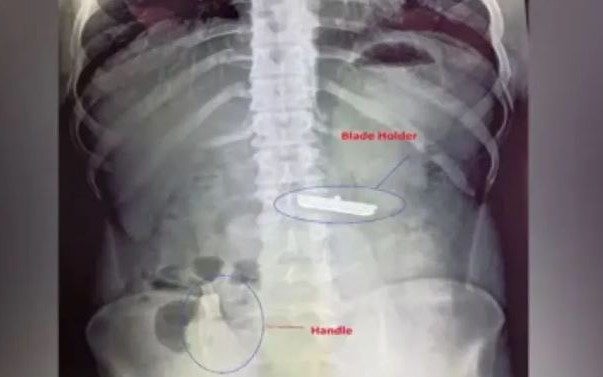

Dị vật được gắp ra trong cơ thể bệnh nhi. Ảnh: Ngô Phúc/VietNamNet

Các bác sĩ nhanh chóng gây mê, nội soi cấp cứu, phát hiện một mảnh nhựa nằm trong thực quản bệnh nhân nên đã gắp ra ngoài.

Bác sĩ Ngô Văn Phan, Trưởng khối liên chuyên khoa, Bệnh viện Nhi đồng Đồng Nai cho hay: Nếu để dị vật lại lâu hơn trong thực quản bệnh nhi có thể gây viêm thực quản, áp xe, thậm chí dẫn đến viêm trung thất, nguy hiểm đến tính mạng. Dị vật này là một mảnh nhựa nhỏ mỏng, trong suốt nên rất khó phát hiện. Đặc biệt, dị vật này ít cản quang, rất khó phát hiện trên phim X-quang.